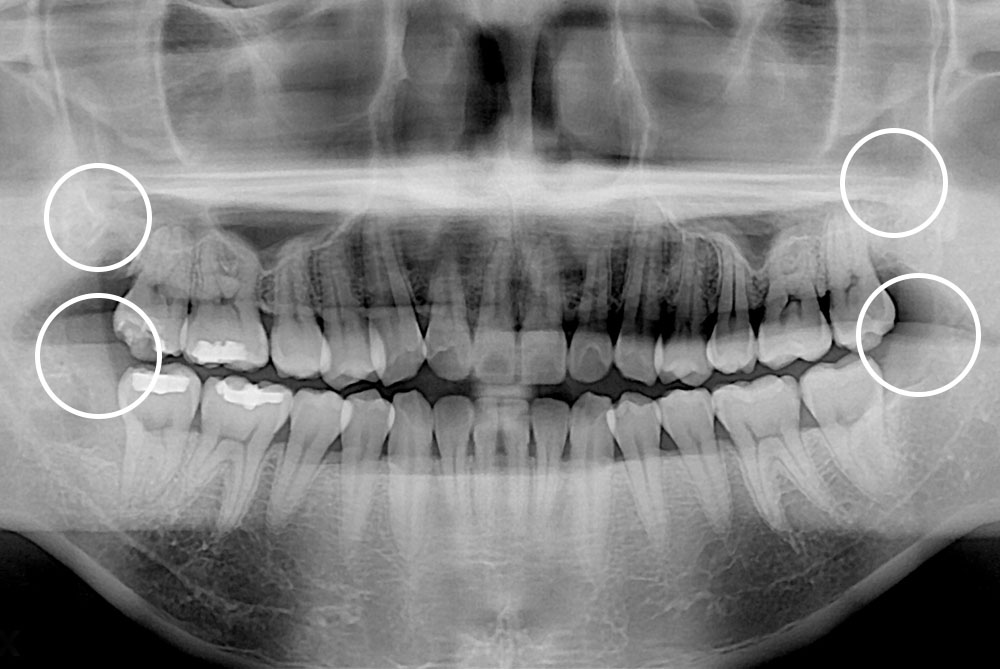

[사랑니] 매복 사랑니 발치

치료후 : 2019-12-19

세종치과는 구강악안면외과학 박사이신 원장님이 발치하는 치과입니다.